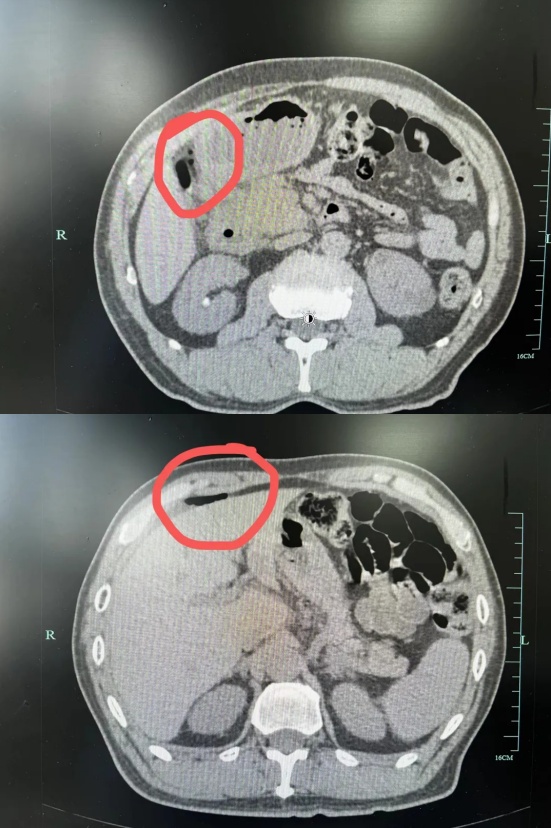

结合病史安排了全腹部CT检查

检查结果显示

王大伯腹腔内有明显的游离气体

和液体集聚

徐主任诊断为消化道穿孔